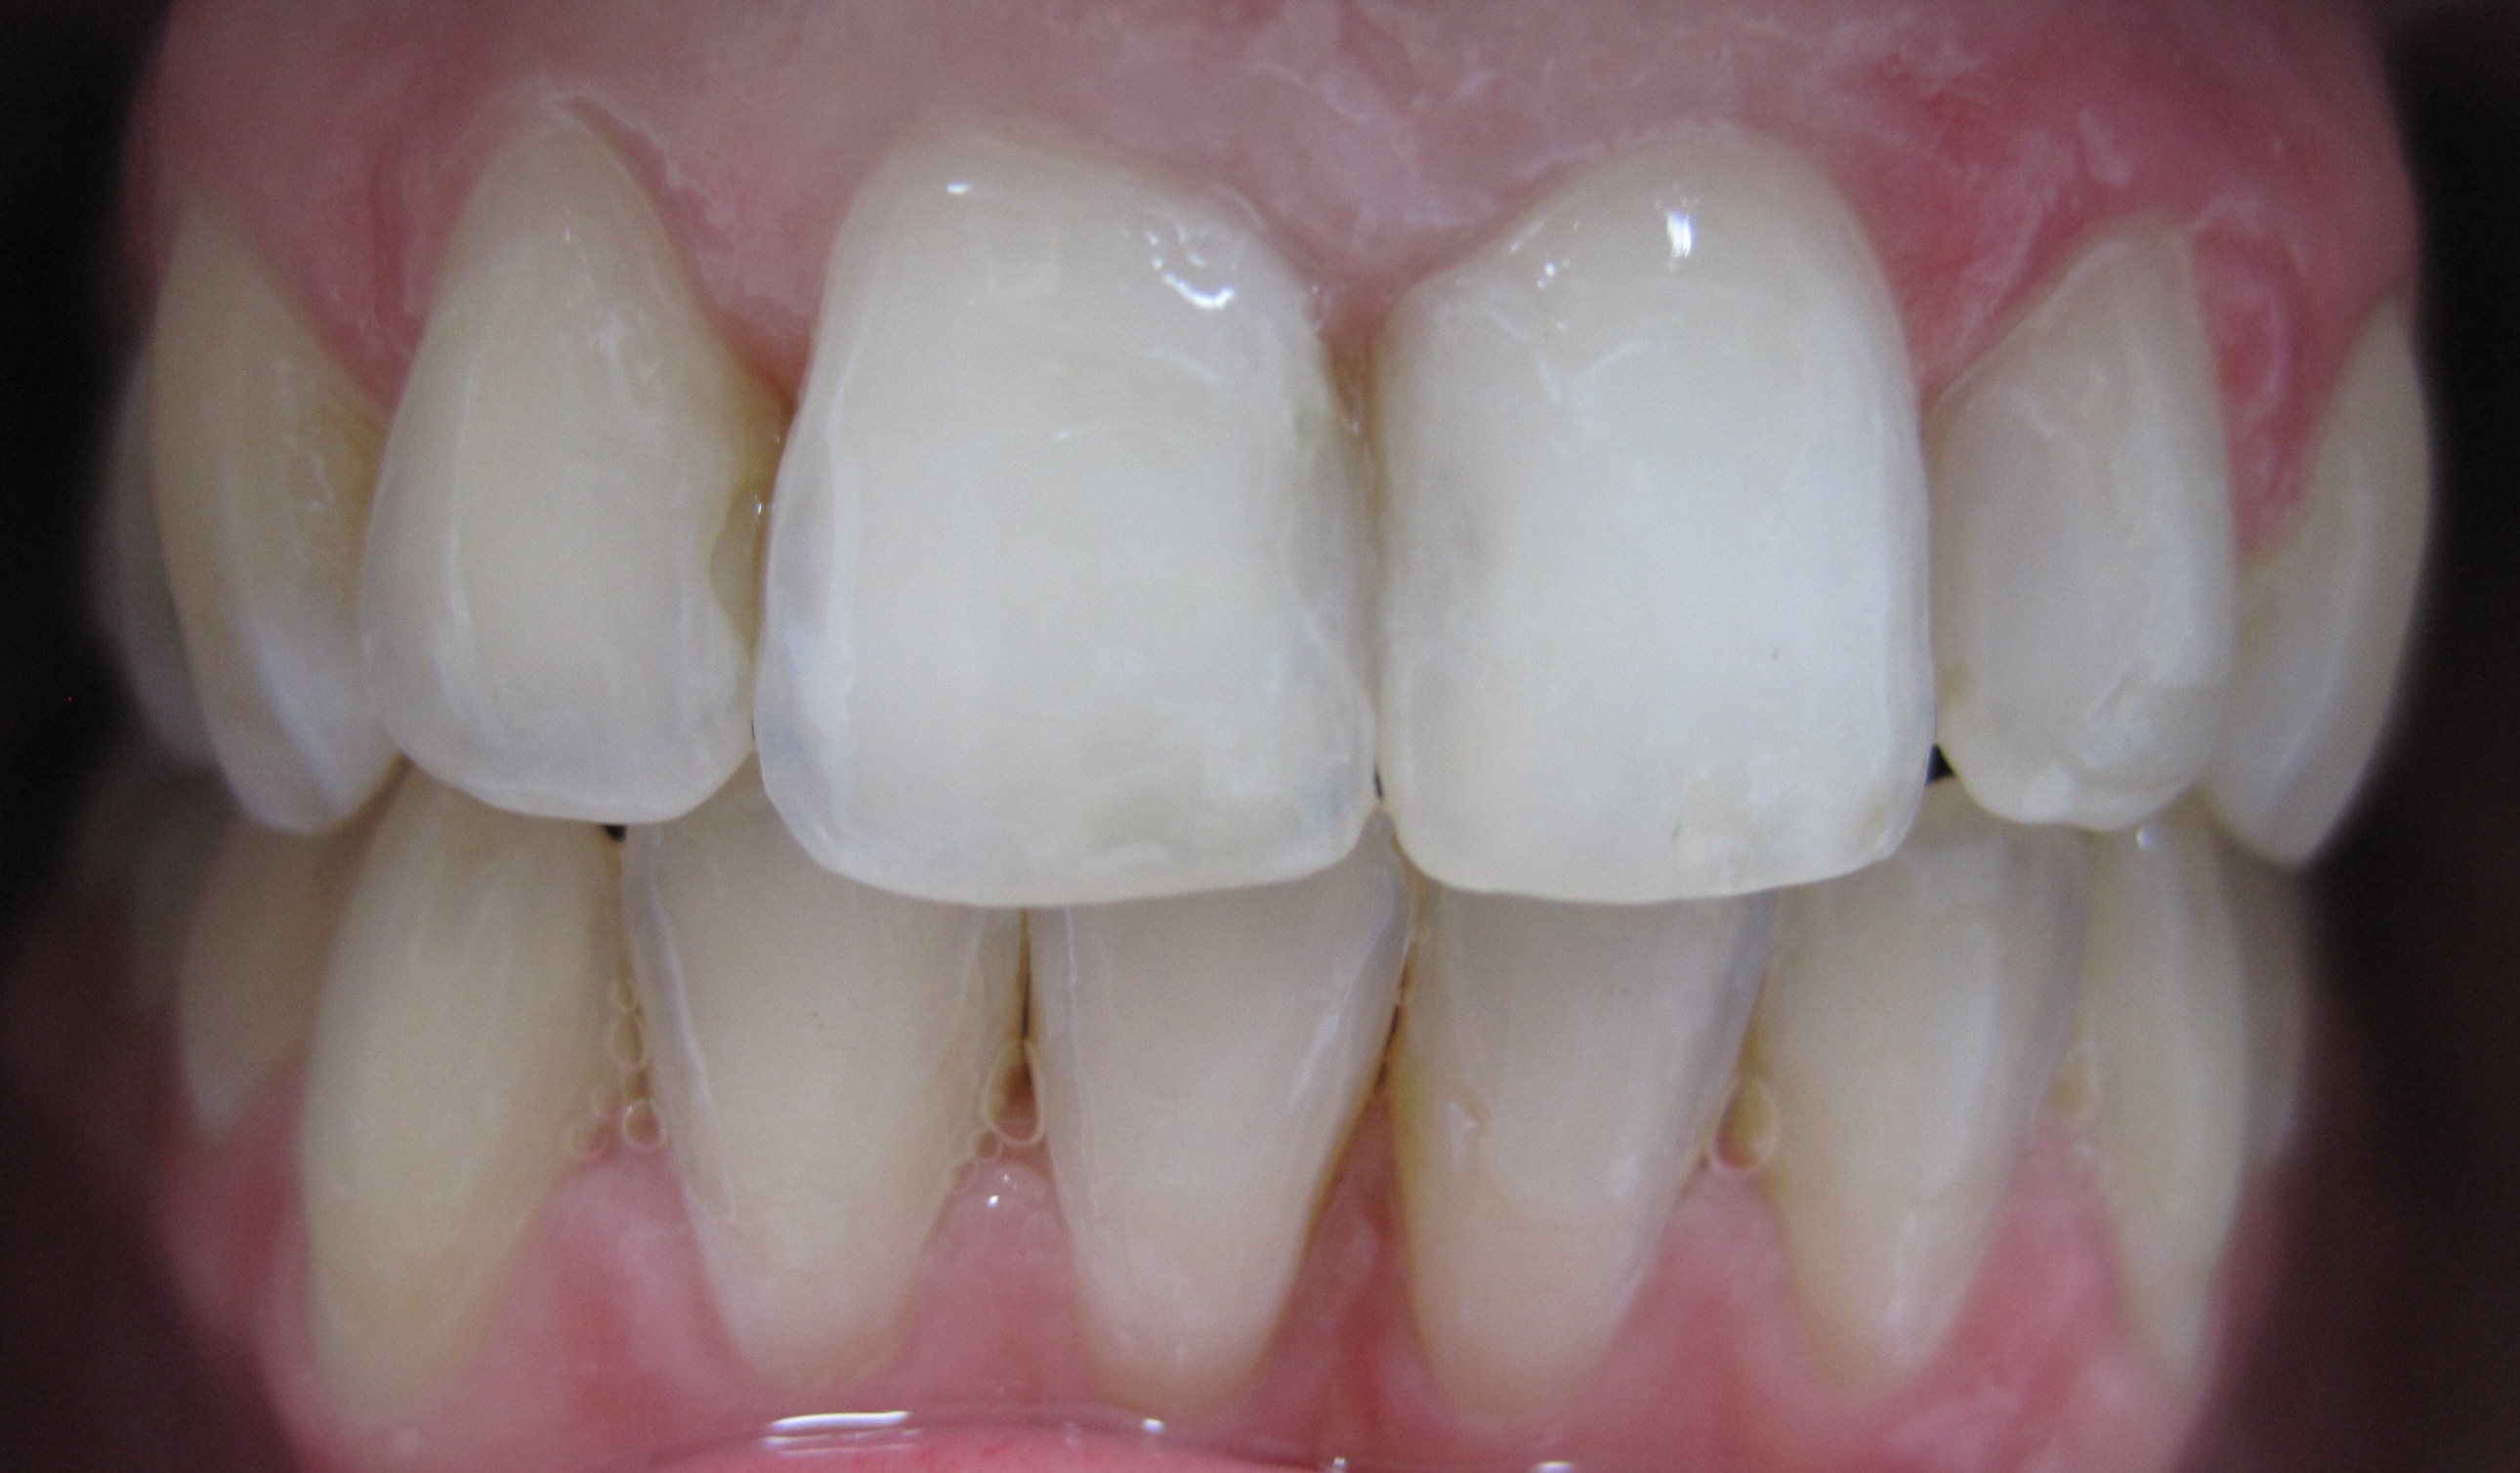

Patient 41 Jahre, massiver Unterkiefer-Frontzahn-Engstand: Alphalignbehandlung mit 15 Alphalignern, d.h. 7,5 Monate Behandlungszeit, jetzt viel bessere Pflege möglich, da akkurater Zahnbogen, dadurch geringeres Risiko von Karies sowie Zahnfleisch- und Zahnbetterkrankungen

nachher (nach 7,5 Monaten Behandlungszeit)